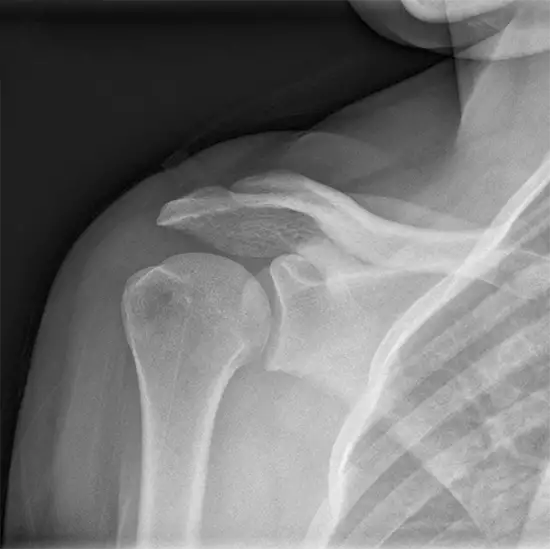

X-Ray Right Shoulder Oblique View is a radiography procedure that is used to examine the shoulder joint in greater detail. For this view, the patient is rotated 35-45 degrees, and his scapular body(back) is up against the imaging detector. This view is helpful in the detection of injuries or fractures to the right shoulder joint.

Doctors recommend this procedure to view the shoulder joint in greater detail to detect shoulder joint injuries, deformities as well as the problems such as shoulder joint dislocation, and frozen shoulder.